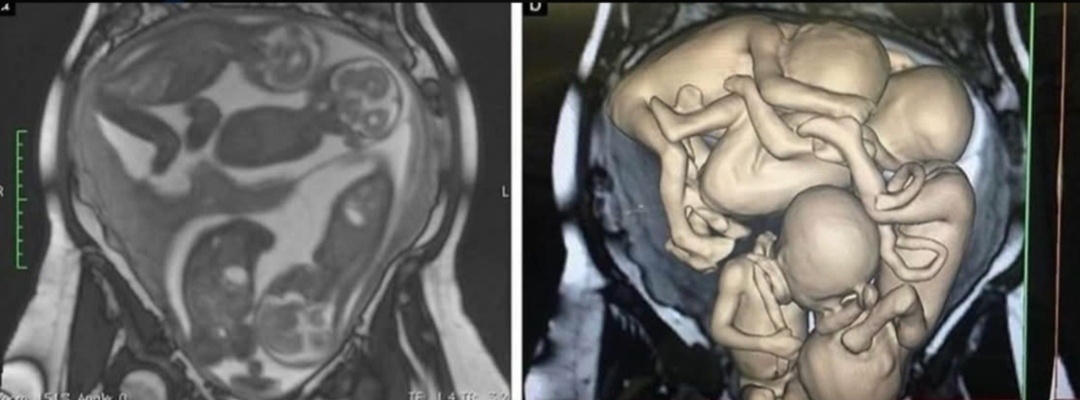

Беременность была очень трудной. На 16-й неделе мне наложили шов на шейку матки, чтобы предотвратить преждевременные роды. С 24-й недели я постоянно принимала прогестерон. На 26-й неделе из-за того, что на УЗИ было плохо всех видно, мне сделали МРТ. Мы даже получили на память 3D-модели наших мальчиков.